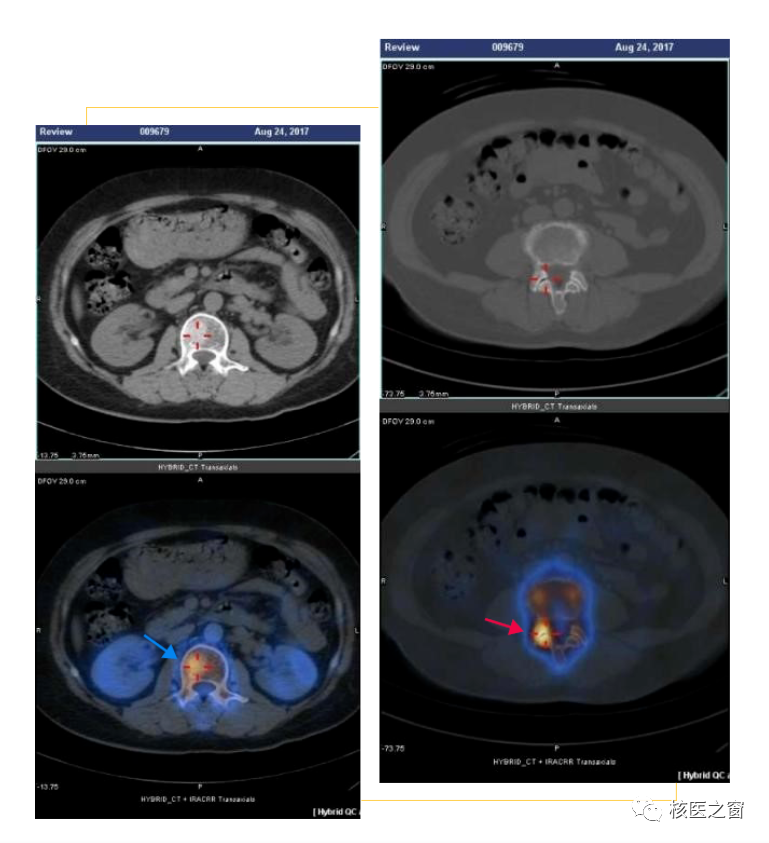

如圖所示,一位中老年乳腺癌患者在術后常規復查全身骨掃描時,發現腰椎邊緣水平有兩處顯像劑濃聚灶(箭頭所示),單從骨掃描無法明確病灶的準確位置和性質(轉移?老年性退變?)。進一步加做局部的臟器斷層顯像(SPECT/CT)后,影像顯示腰2椎體骨質代謝增高灶位于椎體內,局部骨質密度增高,診斷為轉移灶,而另一處病灶定位于腰3-腰4右側椎小關節,結合關節面骨質硬化,診斷為關節退行性改變。

如圖所示,肝癌患者,腹盆部CT沒有發現骨質密度、結構的異常,未提示轉移。但全身骨顯像及臟器斷層顯像(SPECT/CT)顯示左側肱骨頭、胸腰椎多發椎體、左側髖臼、左側股骨上段多發骨質代謝增高灶,診斷多發骨轉移。